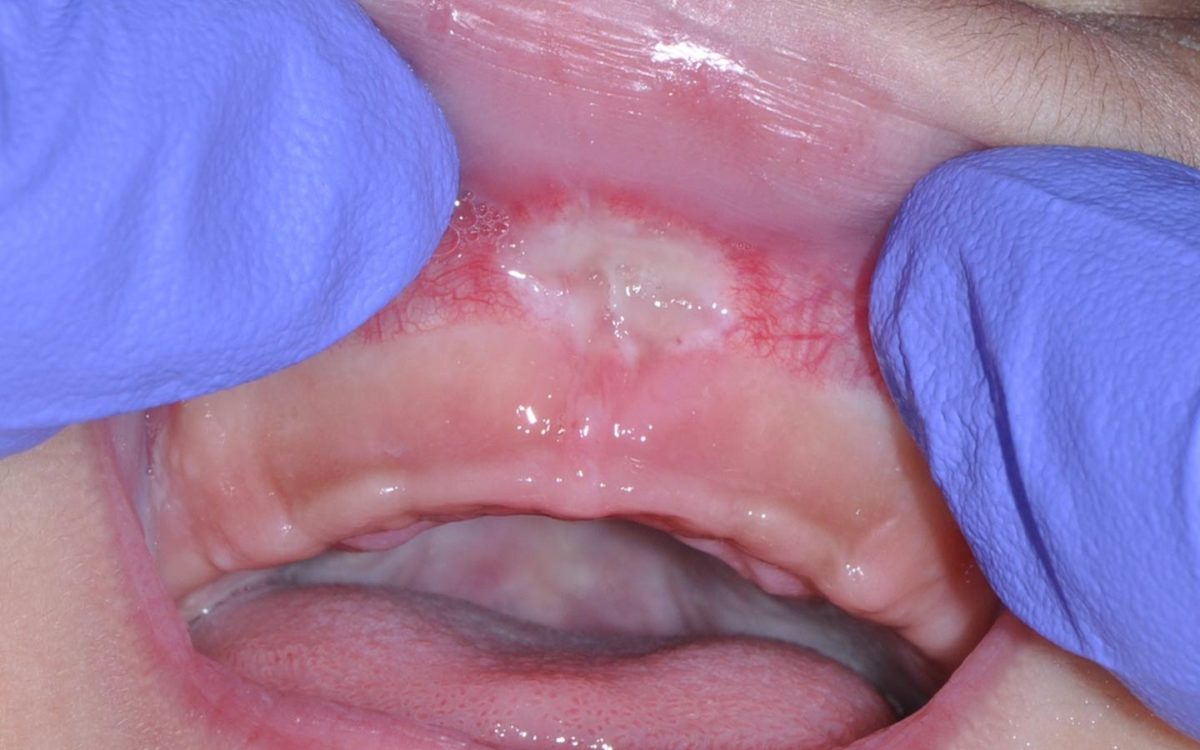

Lip Tie How to Check Your Baby (And How to Fix it)

Does Fixing A Lip Tie Hurt . The procedure to correct a lip tie is called a frenectomy. Here's how to identify a lip tie and fix this common issue. a lip tie occurs when the tissue joining the upper lip to the gum is very tight or short. lip tie removal: In babies, this can cause. understanding the condition and its impact. Will it hurt my baby? Lip tie, a condition less frequently discussed than tongue tie, is an. It's an outpatient procedure, meaning infants do not need to be admitted to the hospital overnight. though it can affect breastfeeding, most conventional doctor's can't recognize a lip tie.

Here's how to identify a lip tie and fix this common issue. lip tie removal: Will it hurt my baby? a lip tie occurs when the tissue joining the upper lip to the gum is very tight or short. In babies, this can cause. Lip tie, a condition less frequently discussed than tongue tie, is an. understanding the condition and its impact. The procedure to correct a lip tie is called a frenectomy. It's an outpatient procedure, meaning infants do not need to be admitted to the hospital overnight. though it can affect breastfeeding, most conventional doctor's can't recognize a lip tie.